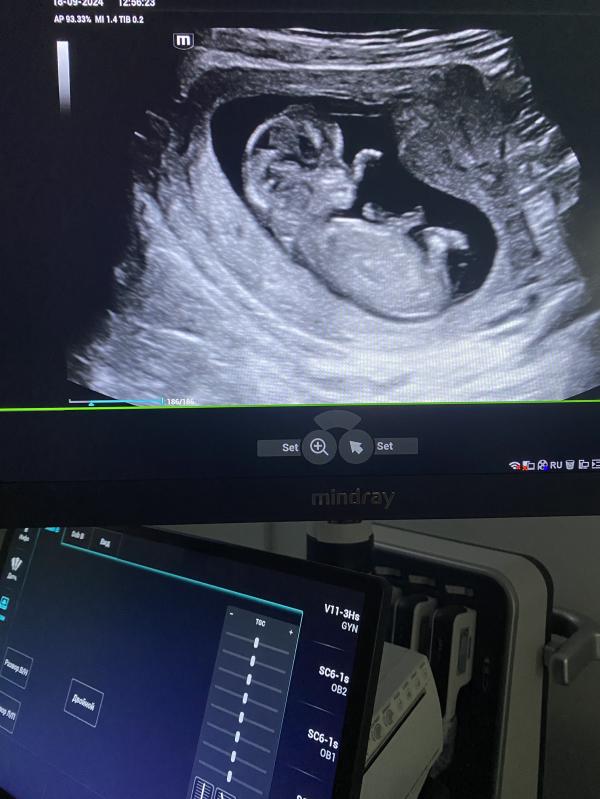

УЗИ беременности: когда делать первое, что показывает и как подготовиться? Советы для будущих мам

Узи беременности